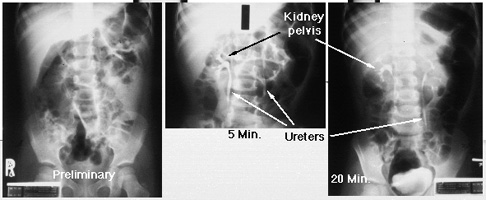

The preliminary film (on the left) is also called a 'scout film.' It is taken before intravenous contrast is given. This first image shows normal bones and soft tissues. Most kidney stones would be visible on the scout film. After contrast is injected intravenously, concentration of the contrast is seen in both kidneys (middle image - nephrogram phase). Contrast may also be seen in the proximal ureters. At 20 minutes after contrast injection (right image), urine containing contrast material is seen to drain through normal sized ureters into the bladder.